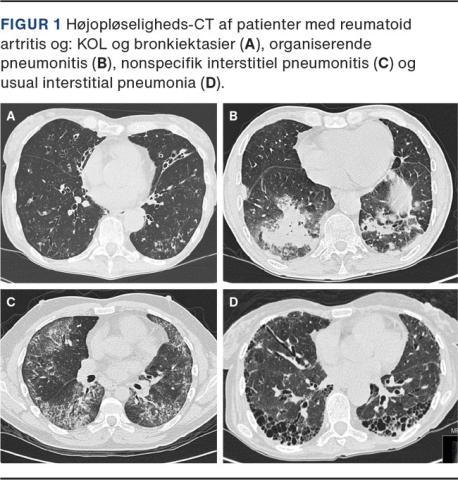

Ved RA ses et bredt udsnit af forskellige HRCT-mønstre. Det hyppigste er usual interstitial pneumonia (UIP), efterfulgt af non-specific interstitial pneumonitis (NSIP) og organiserende pneumonitis (OP) (Figur 1) [15]. Bronkoskopi med bronkoalveolær lavage og lungebiopsi har ingen diagnostisk eller prognostisk værdi ved RA-associeret ILS og anbefales ikke rutinemæssigt, men kan have differentialdiagnostisk værdi til udelukkelse af infektion eller anden patologi.